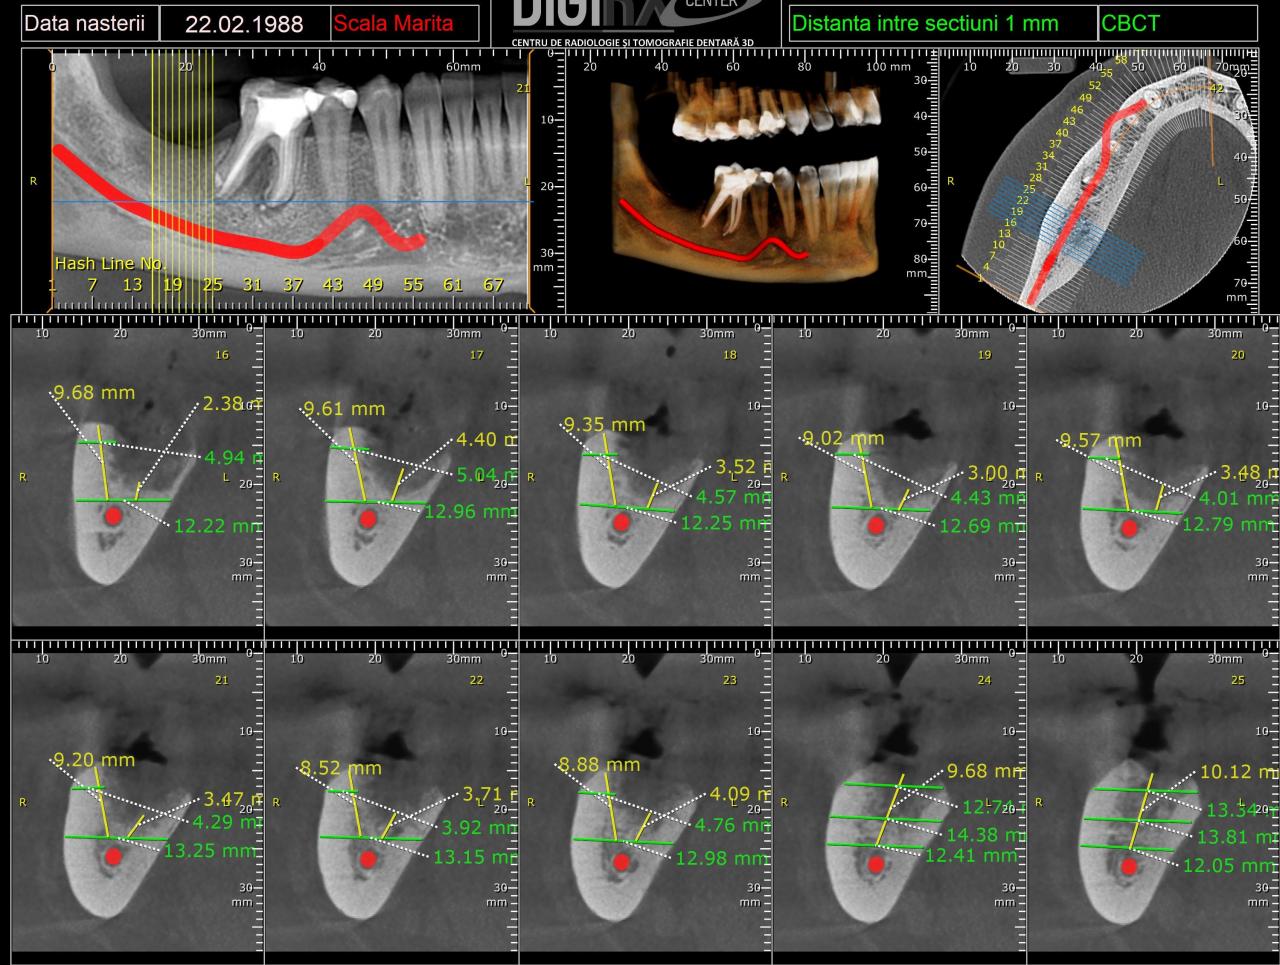

Добрый день. Ищу экспертное мнение. Кто может посмотреть КТ и сказать шо там как. А то я запуталась

Показать скрытый текст

тык

Цитата Сообщение от Zara20 Посмотреть сообщение

Здравствуйте.

Места под имплантант маловато, разве что, на маленький 8 мм

Шестерка с воспалительным процессом. Только вопрос в том, когда она лечилась... Если до 1-3 мес. назад, то можно еще понаблюдать за "восстановлением", если же - 1 год и позже, тогда все очень печально...

Цитата Сообщение от eugtar Посмотреть сообщение

Спасибо за ответ. 6ку давно лечили. Я хотела удаление двух зубов и импланты. Подскажите пожалуйста как сейчас правильно поступить. На 7ку можно "нарастить" кость? А 6 тогда удалять и потом два импланта сразу ставить? Или как правильно?

Если правильно, то нужно смотреть в кресле)

Теоретически 6-ку можно удалять не всю, а только проблемный корень, а дальше – есть варианты восстановления. Но опять же – нужно видеть…

С наращиванием кости уже сложнее, но если задаться целью и при наличии финансов, то можно пробовать что угодно…